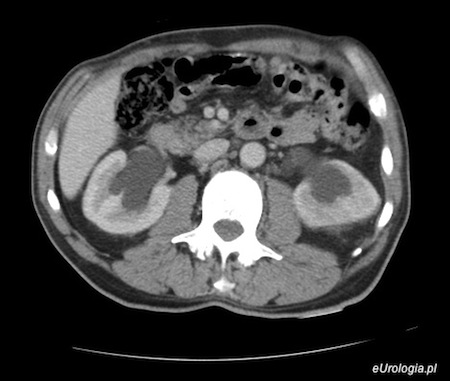

Fot. Wodonercze obustronne - obraz w CT jamy brzusznej

Dwa dni temu mój mąż trafił do szpitala z powodu osłabienia, duszności i zmniejszenia ilości oddawanego moczu. Od kilku lat mąż choruje na raka gruczołu krokowego. W czasie diagnostyki lekarze stwierdzili u męża obustronne wodonercze. Wodonercze rzekomo spowodowane jest chorobą nowotworową prostaty. Jak wygląda leczenie wodonercza obustronnego? Kreatynina w tej chwili wynosi 4. Czekamy na konsultację urologiczną.

Wodonoercze obustronne w przebiegu raka gruczołu krokowego, jakie zostało rozpoznane u Pani męża wymaga leczenia objawowego. Jeśli pacjent się zgadza możliwe będzie założenie nefrostomii - przezskórnego drenażu założonego do nerki, który umożliwi swobodny odpływ moczu z nerki. W razie potrzeby konieczne będzie rozszerzenie diagnostyki, która pozwoli ocenić czy rzeczywiście pozanerkowa niewydolność nerek jest wynikiem raka gruczołu krokowego.